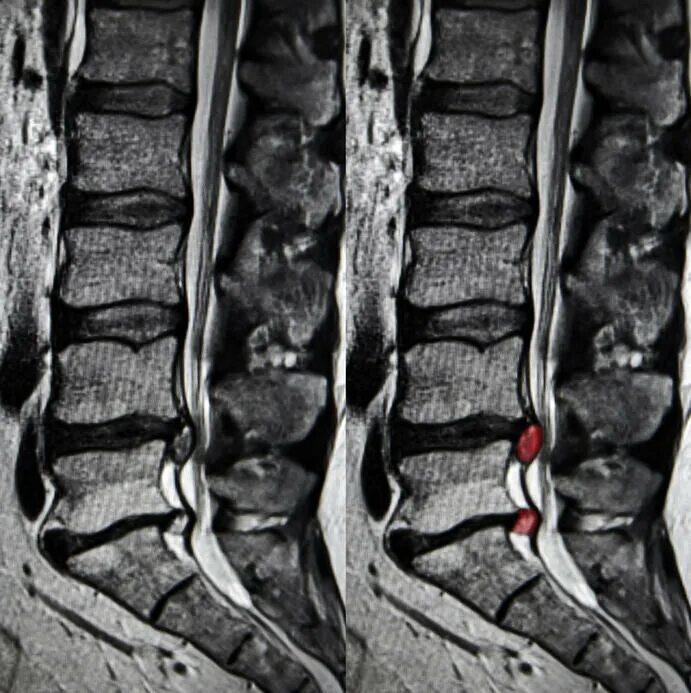

Протрузии дисков с3 с7